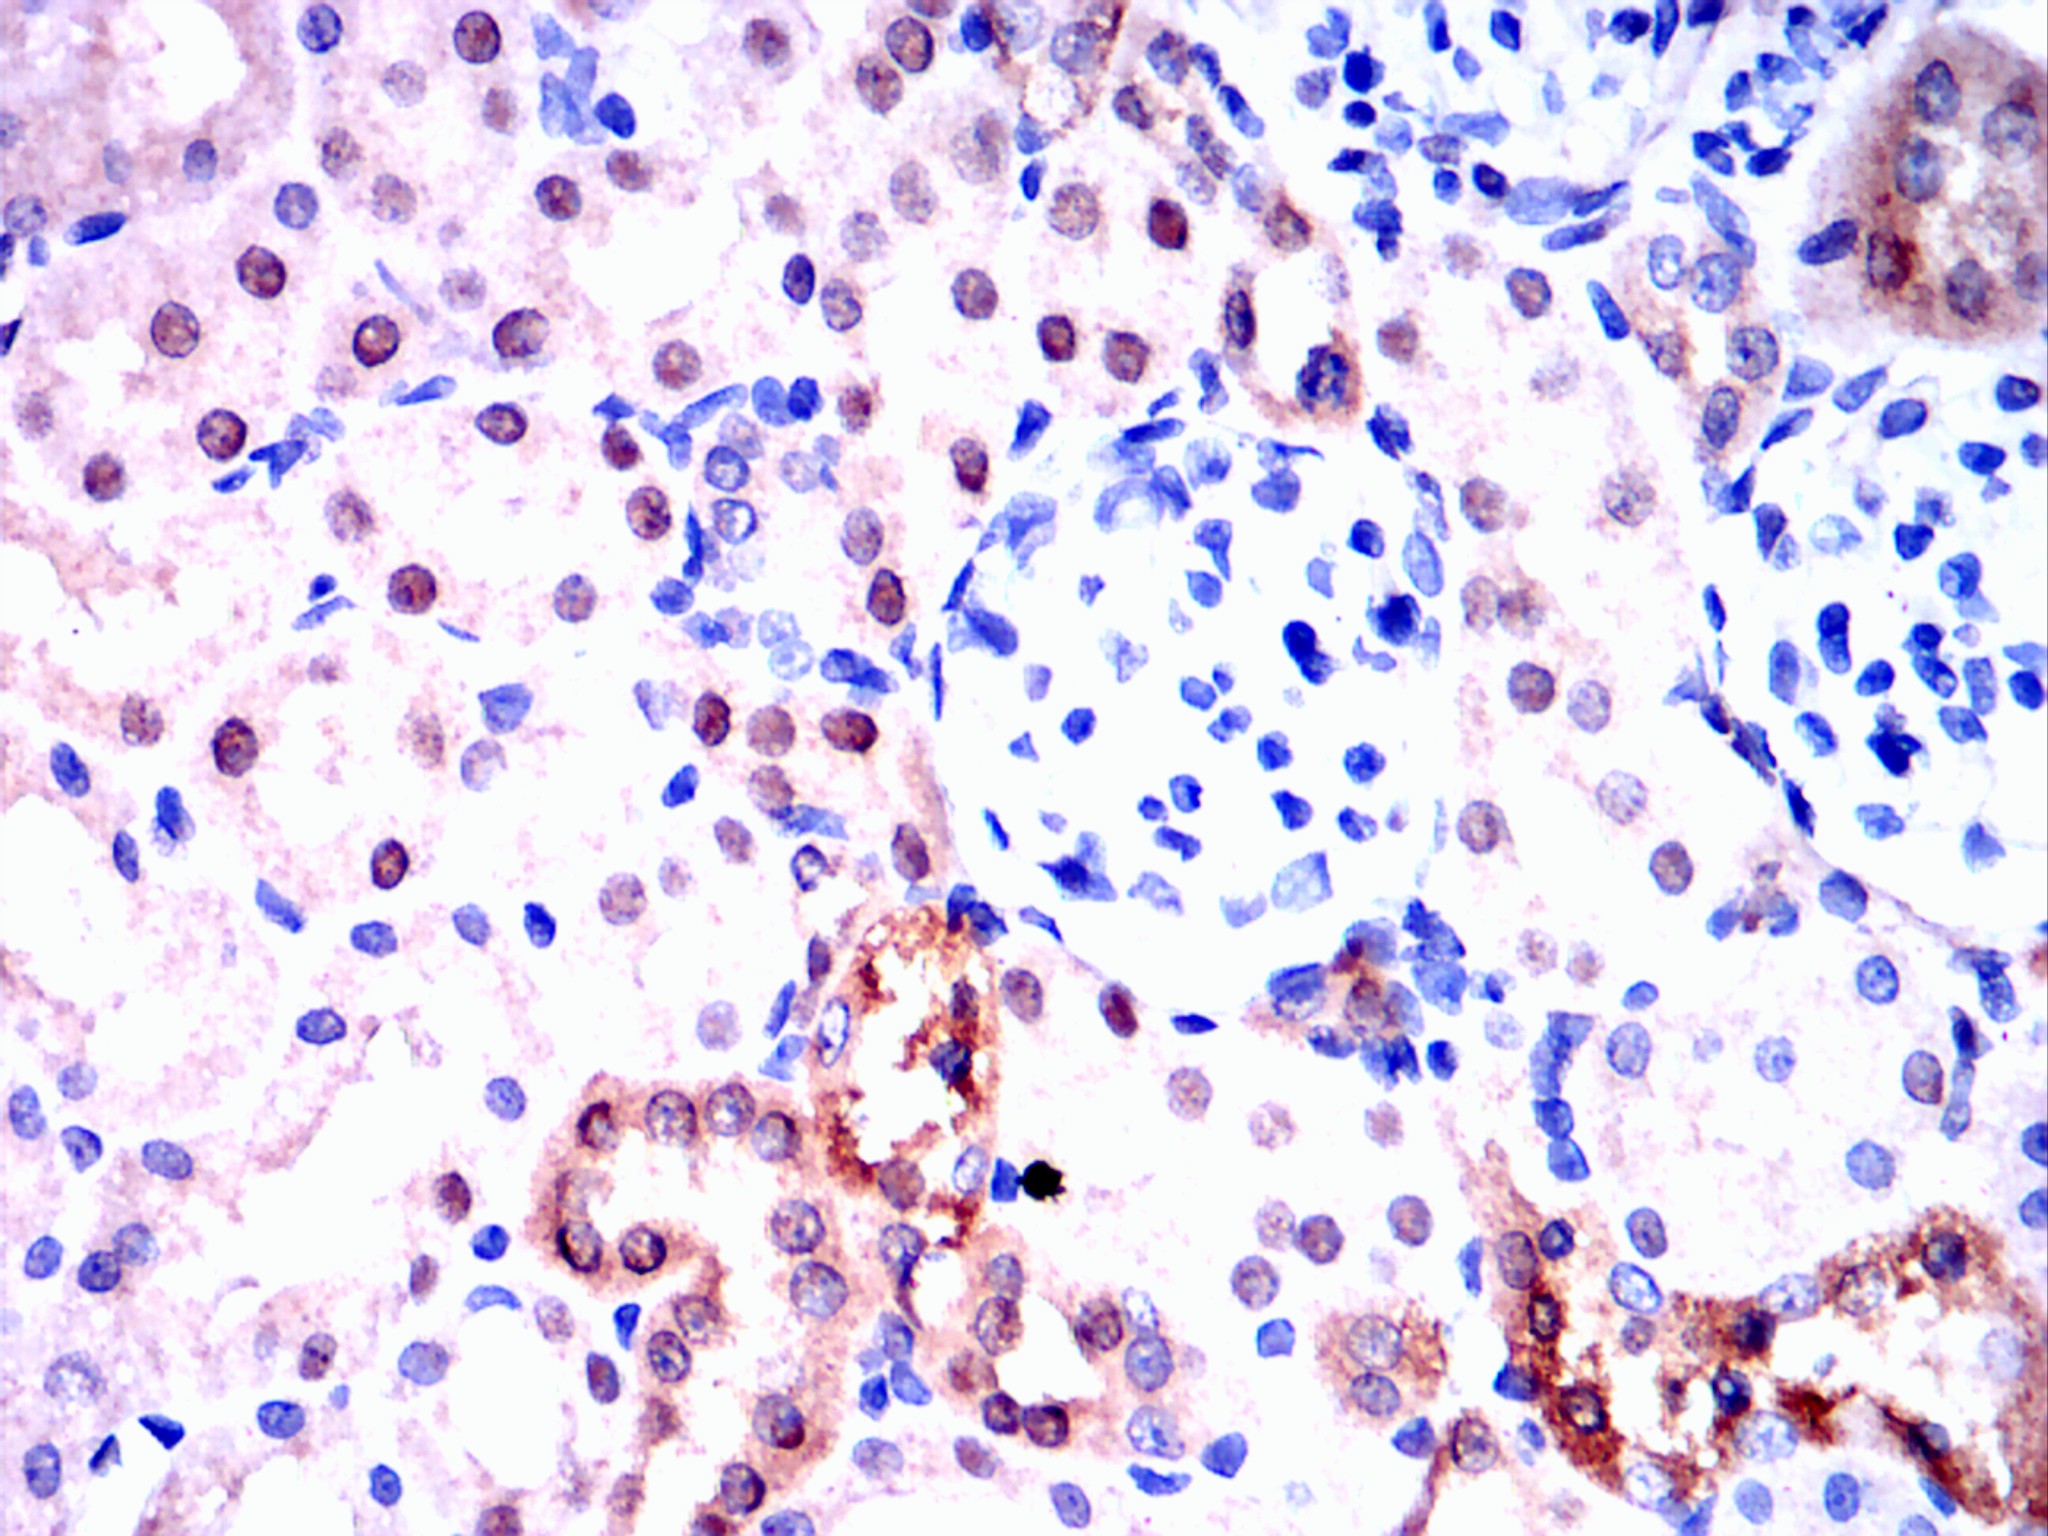

Immunohistochemical analysis of paraffin-embedded rat kidney tissues using Visfatin(PBEF) mouse mAb with DAB staining.